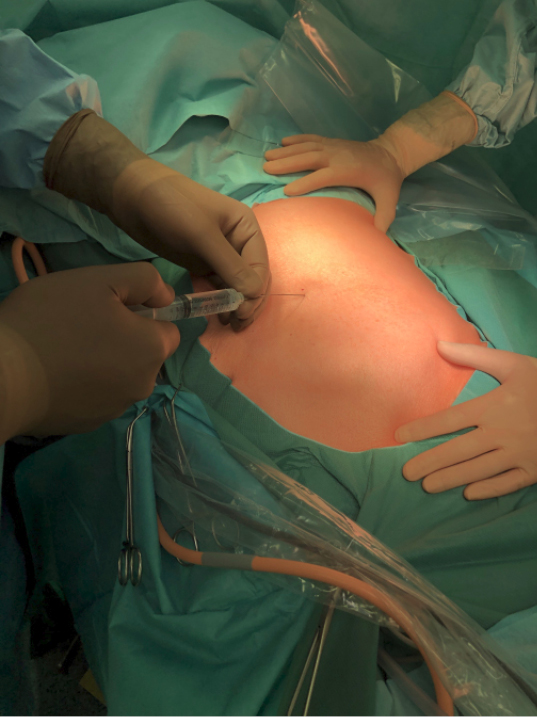

In Sedierung erfahrener, aktiver Anästhesist (nicht bloß „Standby“) –Anxiolytische Prämedikation am OP-Tag –Interkostalblockade am Zugangs-Interkostalraum und seinen Nachbarn (Abbildung 3) –An den Patienten und das Ausmaß der Operation angepasste Sedierungstiefe –Ausreichende Analgesie |

Abb. 3: Setzen der Interkostalblockade im Interkostalraum des geplanten Zugangs und an seinen Nachbar-Interkostalräumen.